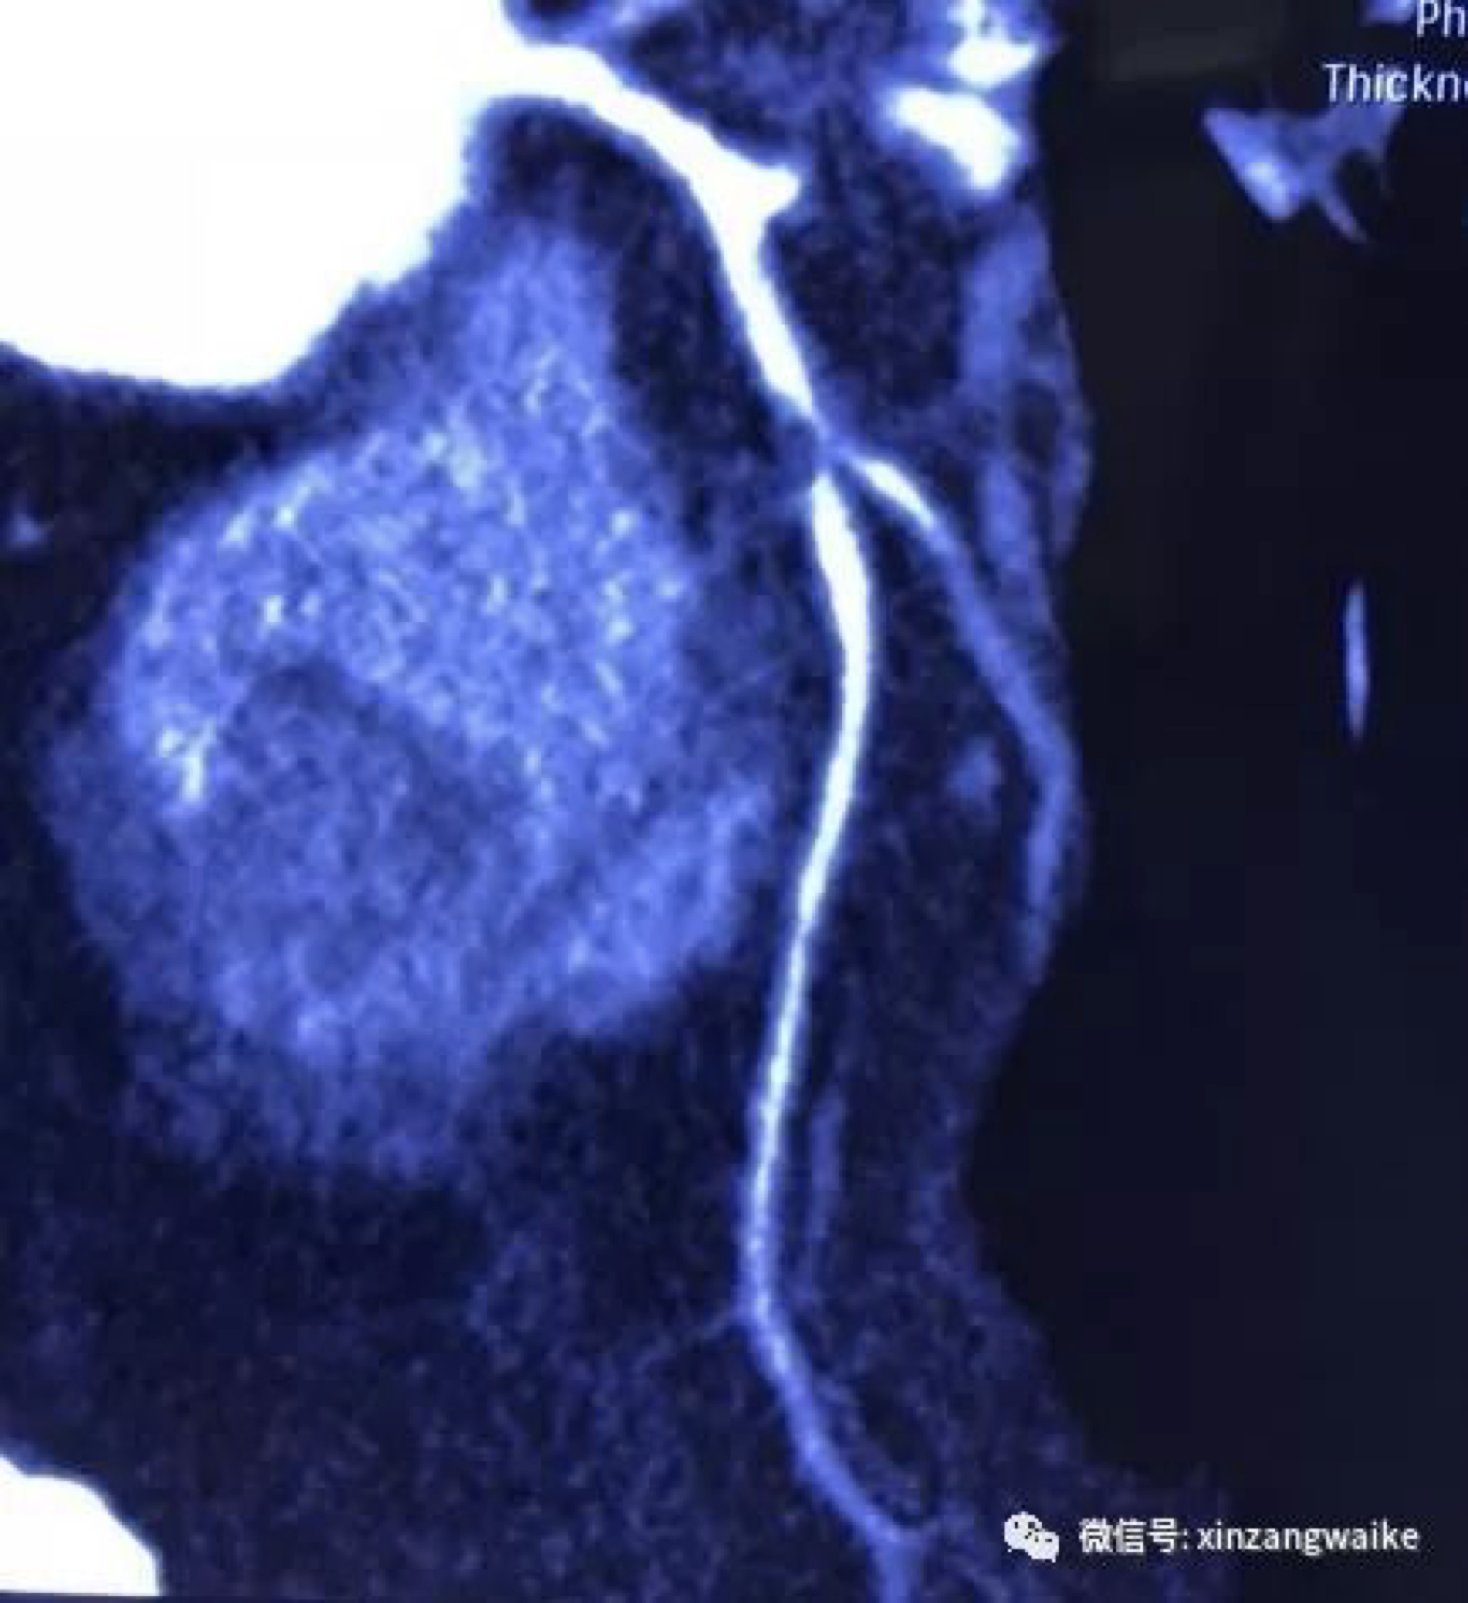

(然而就如上图看到的,肺部肿瘤又刻不容缓)